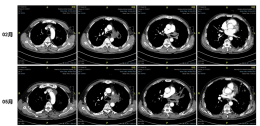

8月患者出现咳嗽、咳痰不利伴反复发热,考虑曲霉感染加重,遂加强抗曲霉治疗,采用伏立康唑联合卡泊芬净,气管镜下对病灶进行两性霉素B局部灌注治疗,同时加用哌拉西林他唑巴坦抗细菌治疗,暂停抗肿瘤治疗。

治疗后患者体温及炎症指标下降,但影像改善不明显,行肺穿刺活检提示慢性炎症细胞浸润,继续维持抗曲霉治疗。9月患者出现少量咯血,经氨甲环酸和蛇毒血凝酶处理后症状缓解。